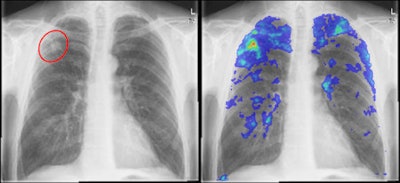

However, CAD might be able to help, serving as a prescreening, triage method for reducing the cost of TB screening algorithms. Since the software yields high sensitivity, it could be useful for performing triage of cases when used as a first reader. Cases found to be normal on CAD would be removed from the screening process, while abnormal studies would then be read by a human expert, Hogeweg said.

It was trained using example of pixels in normal and abnormal regions, with moments of Gaussian derivatives extracted for each region. A classifier is then used to assign a score to each pixel, and each image receives one overall CAD score based on the 95% percentile of all of the pixel abnormality scores, Hogeweg said.

Looking specifically at performance with 95% sensitivity, the CAD software yielded 57% specificity.

"This means that in a triage setting, we can actually discard 57% of the normal images," Hogeweg said. "This also means that in a screening setting where the majority of the images are normal, we can remove a large number of images from the screening process."